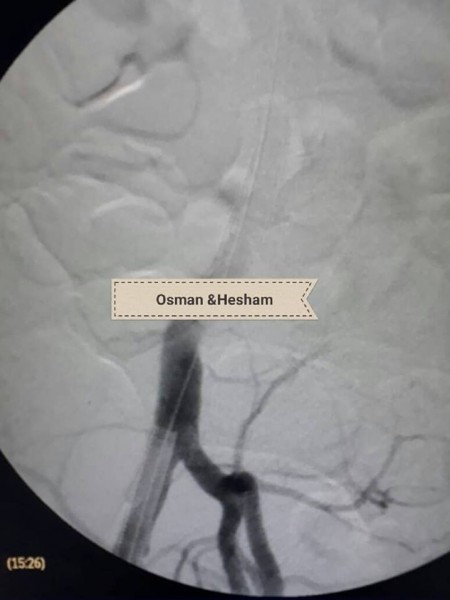

وحول خطوات الجراحة أضاف الدكتور عثمان انه فور إجراء أشعه الدوبلكس للمريض على للشريان الحرقفى الأيسر والشريان الأورطى تبين وجود تمدد ووجود قرحه نشطة بالشريان مع تصلبات شديدة غير مستقرة وانسداد بالدعامة السابقة وكذلك تم إجراء أشعه مقطعية على الشريان الأورطى والطرفين بالصبغة والتي أكدت نفس النتائج ، فكان القرار استخدام دعامات مغطاة للشريان الأورطى والشريان الحرقفى الأيمن وذلك نظراً لأن الوضع الصحي للمريض لا يسمح بإجراء تدخلات جراحية للشريان الأورطى ، ثم تم عمل زرع شريان من الطرف الأيمن للطرف الأيسر لصعوبة شق الدعامة السابقة لاختلاف كبير فى المقاسات التي تم تركيبها للمريض فى وقت سابق .